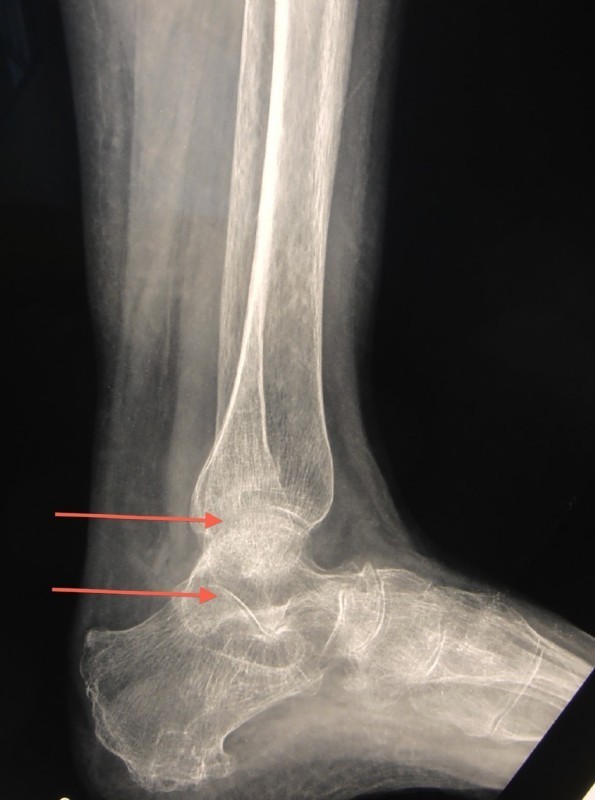

Diese Patientin leidet an massiver Instabilität des ganzen Rückfußes.

Nach einer schweren Verletzung heilten zwar die Knochen, die Bänder aber nicht. Das obere und auch das untere Sprunggelenk sind zerstört. Die Patientin geht schon seit Monaten mit Rollator und entlastet das Bein völlig, weil das Bein sie nicht trägt. Dies führt zur massiven Osteoporose (Knochenerweichung).

Sowohl das obere Sprunggelenk (obere Pfeile) als auch das untere Sprunggelenk (untere Pfeile) sind zerstört und knorpellos. Überdies ist der Knochen durch die Osteoporose buchstäblich so weich wie frisches Brot.